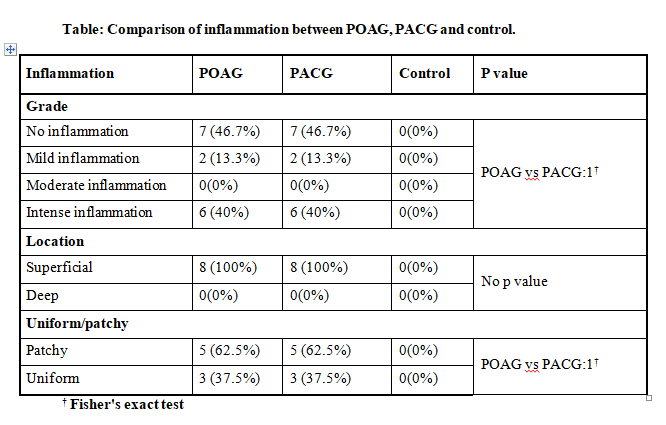

All inflammatory cells were superficial with patchy distribution in 63 %.

Conjunctival fibrosis present in 1/4th (26%) in both POAG & PACG, was mild in 13 % to intense in 40%. Fibrosis in 40 % controls.

Around 47% of glaucoma patients and 100% of control group were found to have no inflammation. Mild inflammation was seen in 13.3% of patients (POAG & PACG group) and intense in 40% (POAG & PACG group). Inflammation was

superficial in all with patchy pattern in 63% & uniform in 38% cases for both POAG & PACG groups. Intergroup comparison of POAG & PACG group NS. A study by Broadway D et al, found that patients briefly treated (AGM duration less